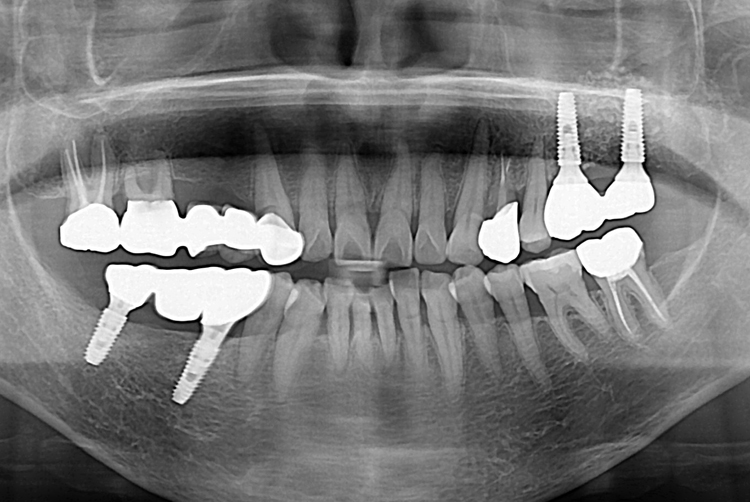

[임플란트] 어금니 임플란트

치료전 : 2019-04-18

세종치과는 많은 환자와 다양한 케이스를 바탕으로

항상 편안한 임플란트 수술을 제공하고자 노력하고,

오래동안 튼튼히 쓸 수 있는 임플란트 수술을 가장 큰 목표로 삼고 있습니다.